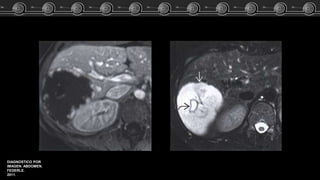

• T1:

hipointensos o isointensos con

RM

• T2:

• T1 + C:

Igual patrón de captación que

en la TC.

Hemangiomas Cavernosos • T1: hipointensos oisointensos con respecto a la sangre. RM • T2: Hiperintensos. • T1 + C: Igual patrón de captación que en la TC.